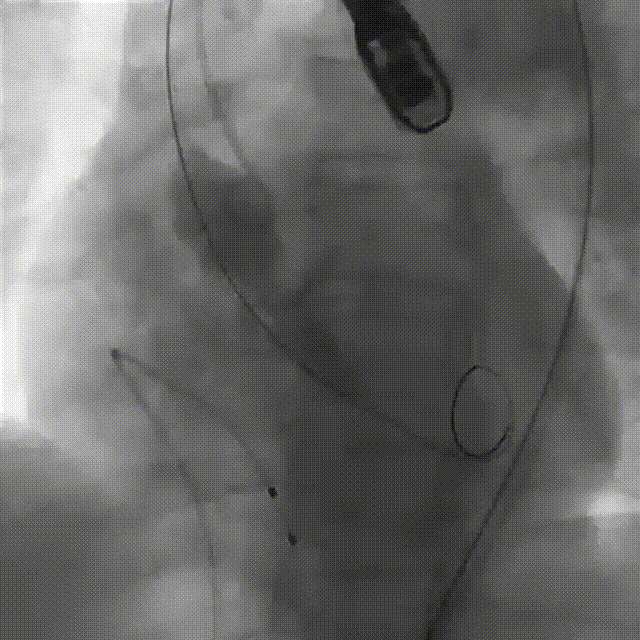

瓣膜初始定位

释放到工作位评估植入深度,

瓣周漏情况

完成瓣膜植入

患者全麻,气管插管。经左侧股动脉作为辅入路,将6F猪尾巴导管送至无冠窦窦底,右股动脉作为主入路,右侧股动脉作为主入路,置入18F大鞘,先行主动脉根部造影,可见术前有轻中度返流,行24mm球囊进行预扩,无瓣周漏,无明显腰征,双侧冠脉血流通畅,决定按计划选择27# VitaFlow Liberty™瓣膜,在王建安教授的线上指导、刘先宝教授的现场支持下,将瓣膜释放至功能位,再次造影发现瓣膜位置偏高,遂进行回收,再次释放,最终脱钩,再次造影确认瓣膜位置及形态良好,压差从术前的80mmHg降低至2mmHg,无瓣周漏。